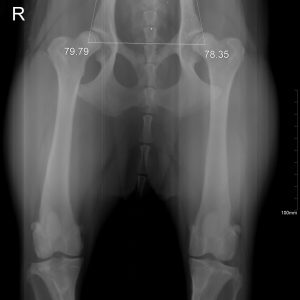

El diagnóstico por imagen es una herramienta fundamental en la medicina veterinaria moderna, ya que permite evaluar de forma precisa y no invasiva las estructuras internas del paciente. A través de técnicas avanzadas como la radiografía digital y la ecografía, es posible identificar alteraciones anatómicas y funcionales que facilitan un diagnóstico temprano y un manejo clínico más eficaz.

Nuestro servicio en Mastervet está orientado a ofrecer estudios de alta calidad, con equipos actualizados y protocolos adaptados a cada caso. Realizamos evaluaciones completas que incluyen la interpretación detallada de las imágenes y la emisión de informes clínicos claros, contribuyendo a la toma de decisiones terapéuticas.

Trabajamos en estrecha colaboración con veterinarios clínicos para asegurar una correcta correlación entre los hallazgos de imagen y la situación clínica del paciente, optimizando así el abordaje diagnóstico y el seguimiento evolutivo.